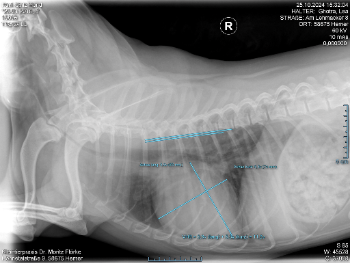

ich wende mich heute mit einer sehr persönlichen Bitte an euch. Mein Hund Paul ist leider herzkrank. Er bedeutet mir unglaublich viel und ist ein wichtiger Teil meines Lebens.

Damit es ihm weiterhin möglichst gut geht, braucht Paul regelmäßig Medikamente für sein Herz und außerdem alle 6 Monate ein Herzultraschall beim Tierarzt, um seinen Zustand zu kontrollieren. Diese Untersuchungen und die Medikamente sind leider sehr teuer und übersteigen inzwischen meine Möglichkeiten.